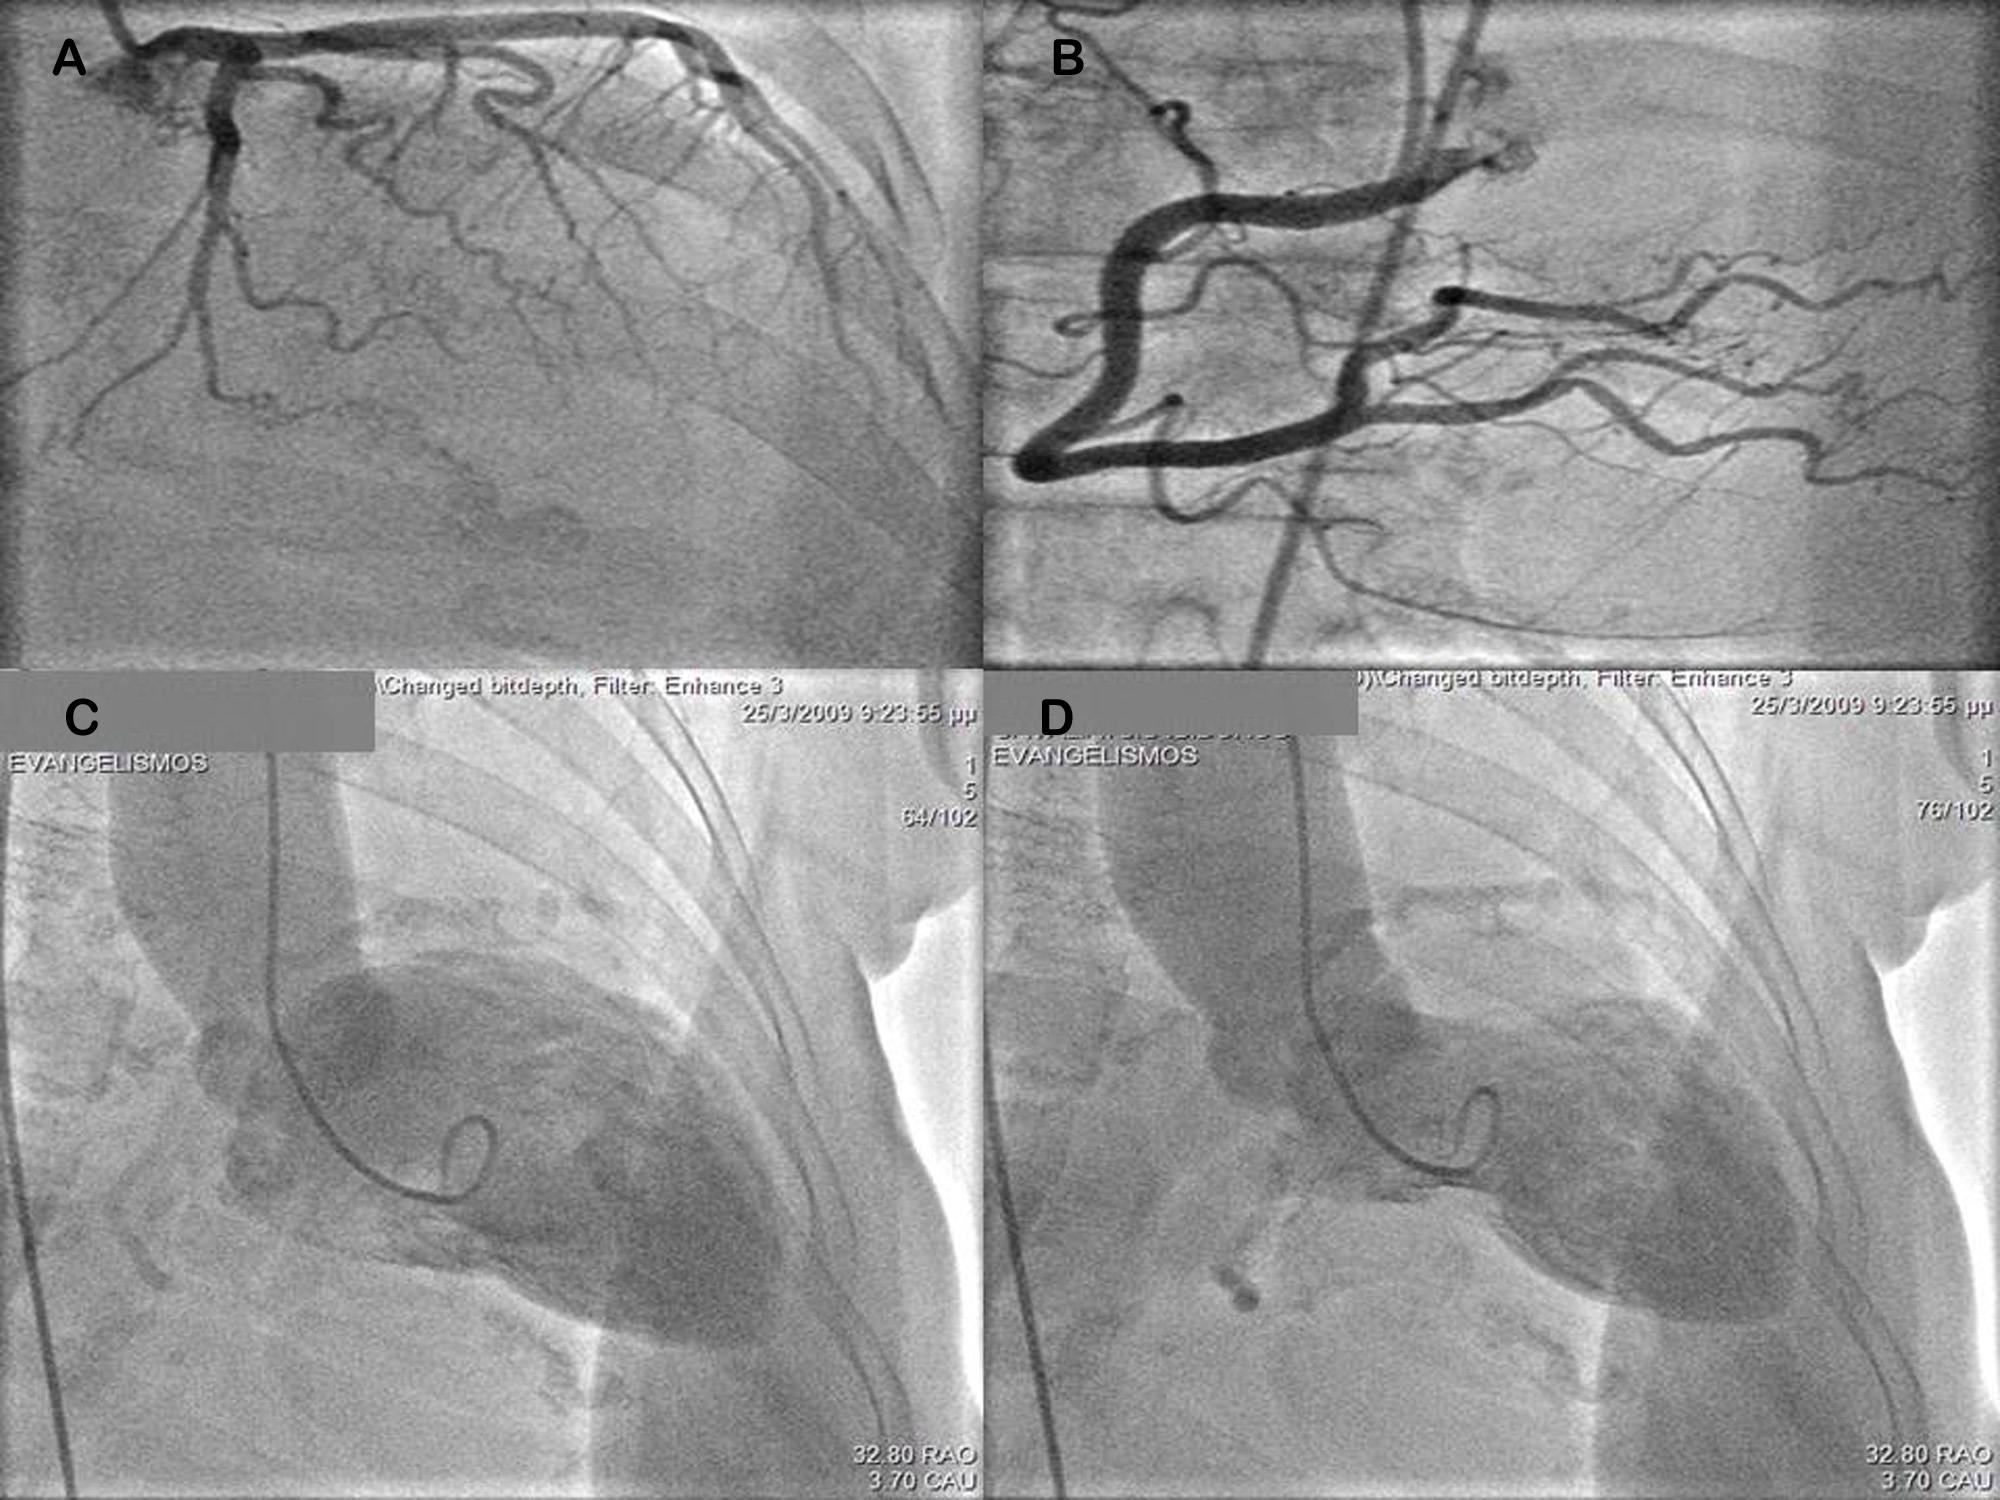

A 68–year–old woman, 4 hours after bronchoscopy, developed symptoms and ECG signs of inferolateral acute myocardial infarction. Emergency coronary angiography showed normal coronary arteries, but LV angiography revealed apical ballooning with apical akinesis diagnostic of Tako-tsubo cardiomyopathy. One day later cardiac MRI additionally disclosed right ventricular apical involvement, which has been reported in only very few cases in the literature associated with worse prognosis. Fortunately, our patient had an uneventful course and complete recovery.Downloads